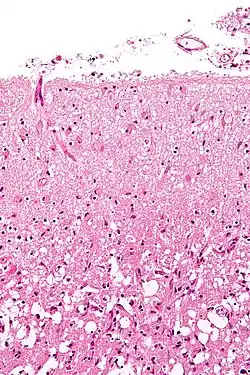

Micrograph showing cortical pseudolaminar necrosis, a finding seen in strokes on medical imaging and at autopsy. H&E-LFB stain.

Micrograph showing cortical pseudolaminar necrosis, a finding seen in strokes on medical imaging and at autopsy. H&E-LFB stain. Micrograph of the superficial cerebral cortex showing neuron loss and reactive astrocytes in a person that has had a stroke. H&E-LFB stain.

Micrograph of the superficial cerebral cortex showing neuron loss and reactive astrocytes in a person that has had a stroke. H&E-LFB stain.